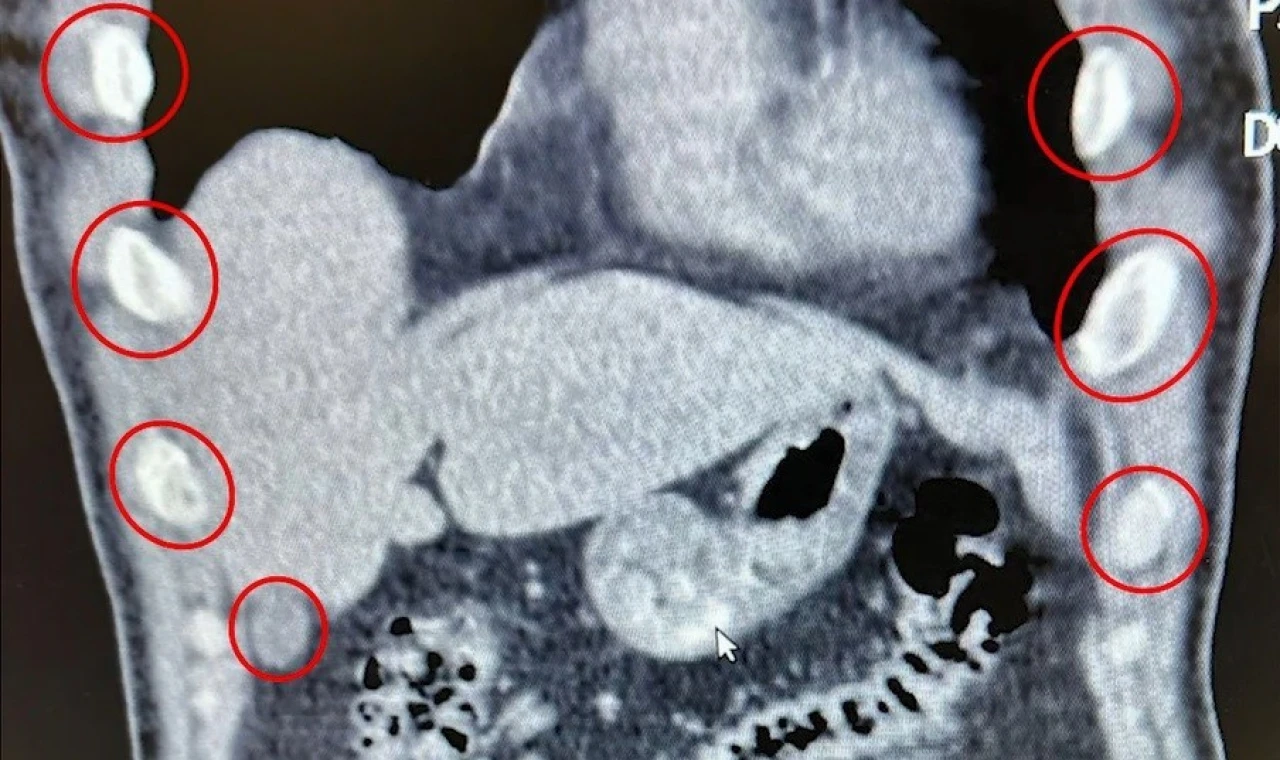

Tatvan ilçesinde durdurulan bir otobüste yolcu olarak seyahat eden yabancı uyruklu 2 kişi gözaltına alındı. Şahısların yapılan tıbbi müdahalesinde, yuttukları 136 kapsül halinde toplam 1 kilo 48 gram metamfetamin ele geçirildi.